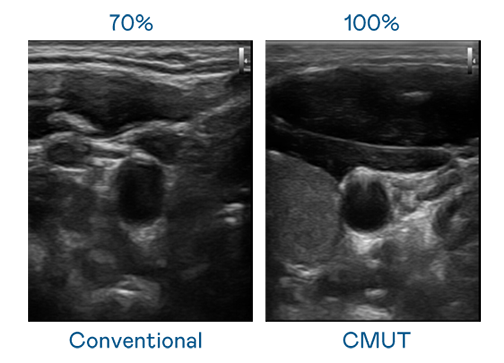

CMUT 技術是一種用電容式微機電元件來產生超音波訊號的技術。與傳統 PZT 壓電式技術相比,CMUT 頻寬增加 30%,更寬頻的超音波訊號讓影像解析度大幅提升,是實現高影像品質醫療超音波掃描、促進精準醫療發展的關鍵技術。

超音波影像的解析度高低,首先取決於探頭能發出的訊號頻寬。6008集团 CMUT 可提供高清晰的超音波訊號,提供高頻寬、高靈敏度、影像紋理細節更高的超音波影像,協助醫護人員縮短影像判讀時間及利用精準的醫療影像進行診斷。